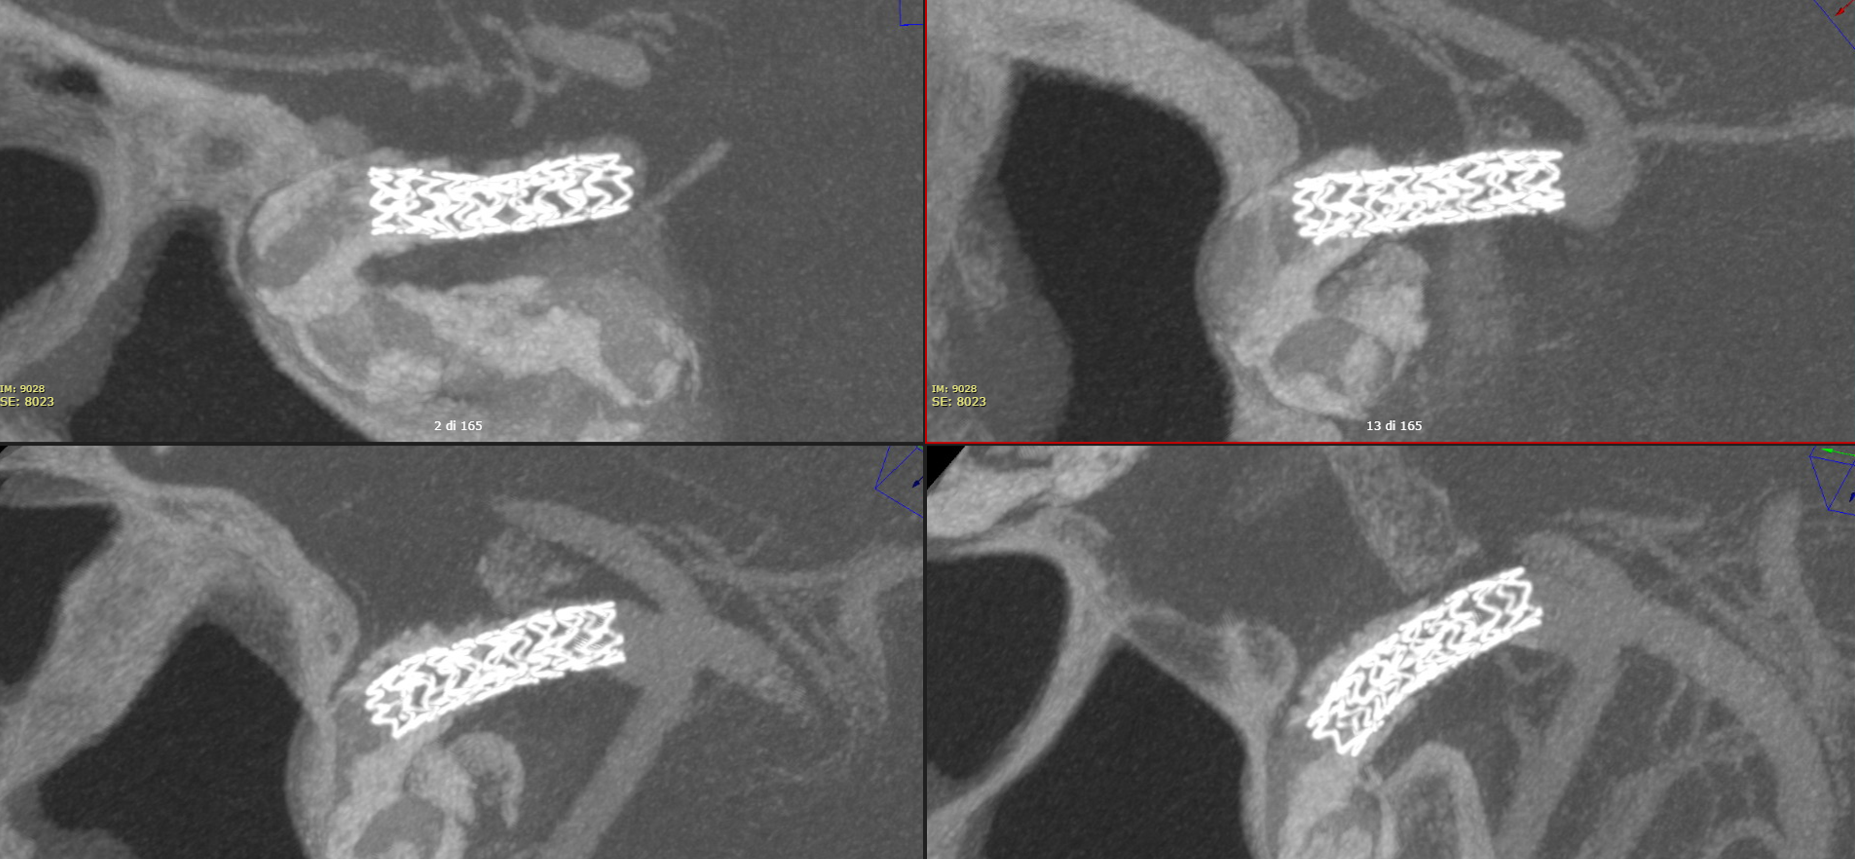

The Vaso-CT (22 cm FOV, 20 seconds acquisition, 20 ml of 50% contrast – 300 mg/ml – manual injection with a 20 ml syringe) clearly defines the lumen of the artery, the plaques and the stent. Note how the plaques were not visible in the pre-stent Vaso-CT (done with pure contrast injection) because covered by the high density of the pure contrast. Thin MIP reconstructions.

Thick MIP recons